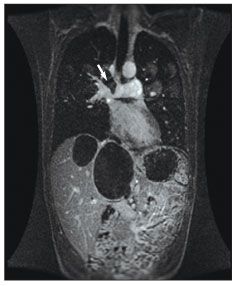

Figure 3 – A magnetic resonance angiogram of the chest demonstrates filling defect (arrow) in the right pulmonary artery extending to the apical branch of the right upper lobe pulmonary artery consistent with the presence of multiple echinococcal cysts. Multiple liver cysts are also seen.

He was afebrile, and findings from his physical examination were remarkable only for a well-healed posterior thoracic scar on the left side and tender hepatomegaly. Laboratory tests revealed a white blood cell count of 8500/µL, with a total eosinophil count of 510/µL; normal electrolyte, bilirubin, and aspartate aminotransferase levels; and a mildly elevated alanine aminotransferase level. Results of a serum antibody test for E granulosus were positive. The chest radiographic findings were normal. A CT scan (Figure 1) and an ultrasonogram (Figure 2) of the abdomen demonstrated multiple daughter cysts in both the left and right lobes of the liver. Magnetic resonance angiography (MRA) of the chest showed multiple intraluminal echinococcal cysts in the right pulmonary artery extending to apical branches of the right upper lobe pulmonary artery (Figure 3).

Our patient had long-standing echinococcal disease involving the liver and lung because of E granulosus infection. Previous lung resection probably caused spillage of scolices and resulted in further extension of his disease, including involvement of the pulmonary artery. His history of poor adherence to albendazole therapy was probably also a factor in the progression of disease. Ultrasonography, CT, and MRA helped define the extent of the patient’s disease preoperatively.